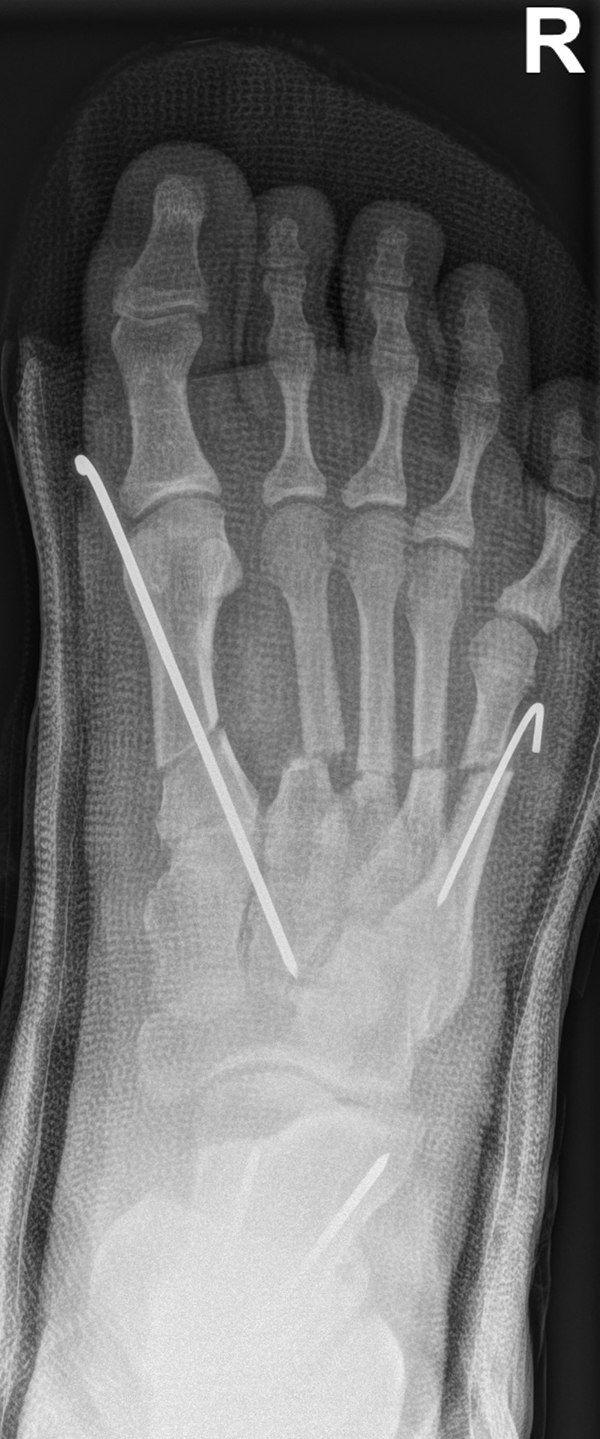

Zusätzlich schränken Wachstumsfugen die Wahl der Osteosynthese ein. Eine die Fuge kreuzende Osteosynthese ist ausschließlich mit Kirschner-Drähten möglich (Abb. 3).

Abb. 3 a-j: Beispiel einer Calcaneusverschiebeosteotomie mit offenen Wachstumsfugen und der entsprechenden Osteosynthese mit Kirschner Drähten. Lokalisation der Osteotomie (a), Lage der Fräse (b-d), Drahtlage mehrere Ansichten (e-h), Heilung der Osteotomie 4 Wochen postoperativ und Entfernung der Drähte (i-j).

Calcaneus-Osteotomie

Die minimalinvasive Calcaneusverschiebeosteotomie bietet eindeutige Vorteile gegenüber dem offenen Verfahren, sodass wir bei Kindern und Jugendlichen nahezu keine offene Verschiebeosteotomie mehr durchführen. Am Calcaneus liegt die offene Wachstumsfuge dorsal. Bei der Durchführung müssen Schenkel der V-förmigen Osteotomie daher etwas steiler angelegt werden, in einem stumpfen Winkel (siehe Abb. 3 a-j). Für die Osteotomie liegen unsere Patienten auf dem Rücken und der BV wird für die exakte Seitaufnahme eingestellt. Der Fuß lagert auf einem hohen OP-Kissen und die Osteotomie kann bequem mit einem langen Kirschner-Draht und einem sterilen Stift angezeichnet werden (Abb. 15).